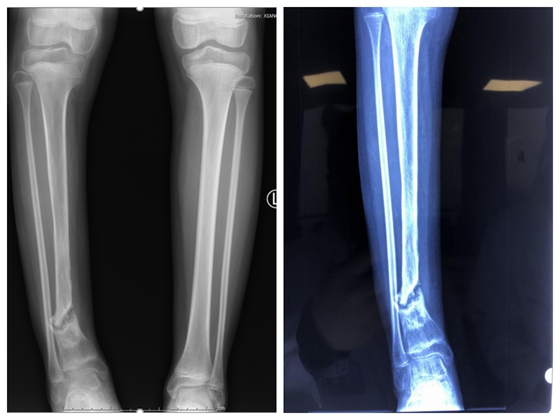

2018年1月,11岁的蓓蓓突然觉得右小腿红肿疼痛,伴有高热畏寒,于当地就诊后诊断为右胫骨急性血源性骨髓炎,但由于对此疾病的认识不足,未及时彻底控制急性骨髓炎的进程,最终发展成慢性骨髓炎并病理性骨折。随后的一年,蓓蓓去到了大大小小的医院,经历了大大小小的手术均未取得好的成效,还曾被专家告知将面临截肢,本该活泼好动的她逐渐变得郁郁寡欢。

入院检查:胫骨骨缺损,骨不连,已完全丧失功能